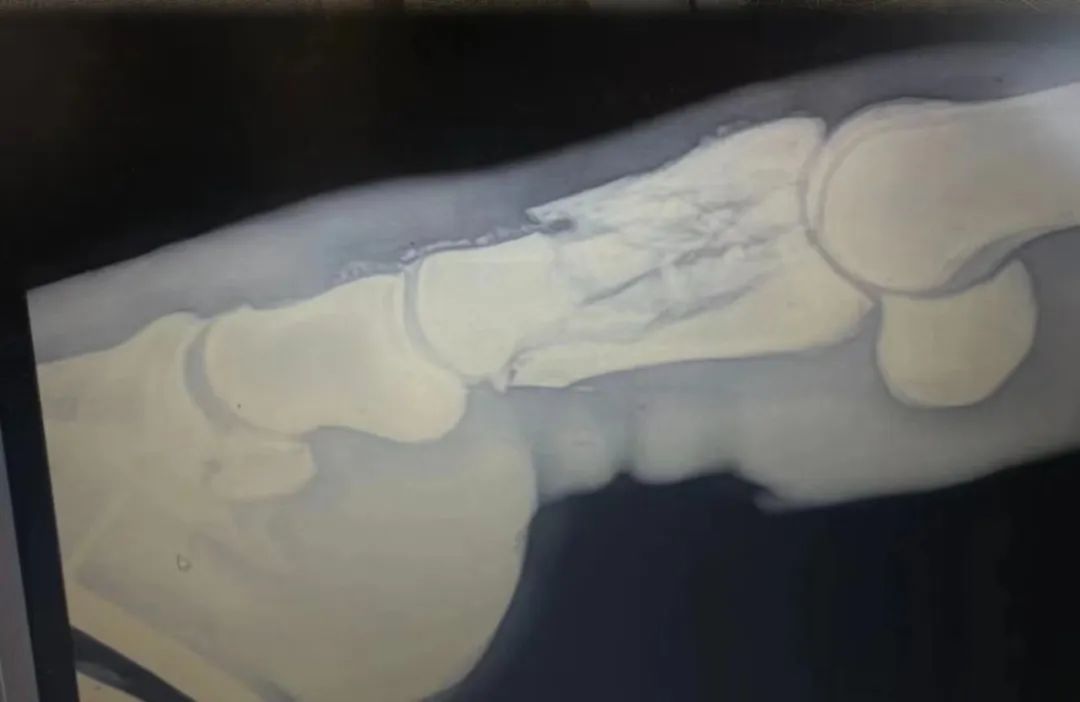

憨子的骨折片子

憨子又这么吊了一周,好消息是X光显示憨子的骨痂长出来了,但效果并不尽如人意。医生告诉张敬宜,如果骨头一直位移,骨痂不能在一个月内长到30-50%,憨子就没有机会了。